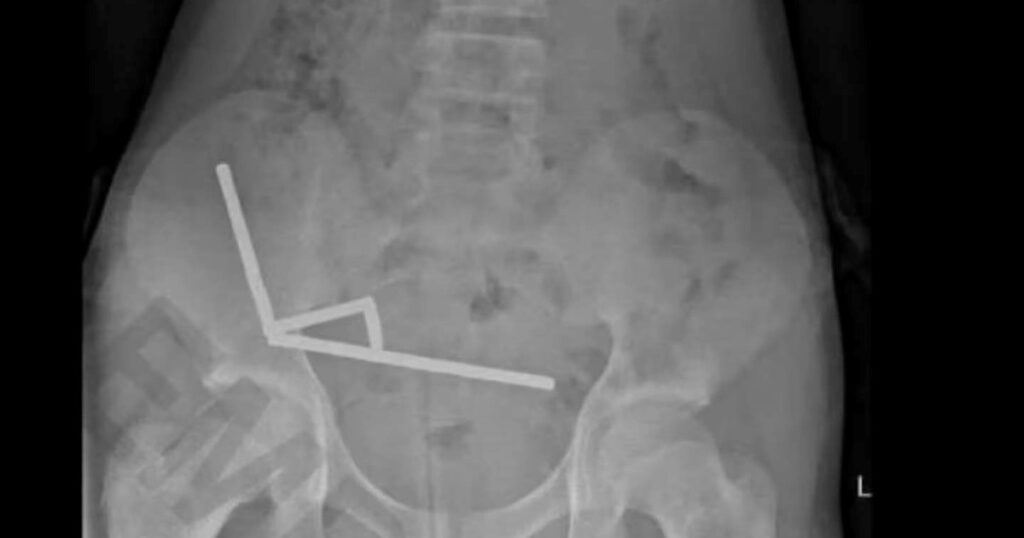

Una radiografía reveló “cadenas” de imanes en distintas secciones del intestino: cuatro agrupaciones metálicas que se habían unido a través del tejido y estaban dañando seriamente órganos vitales.

Los médicos hallaron tejido muerto en el interior del niño debido a la compresión magnética. Foto: New Zealand Medical Journal

Tal fue el caso: los médicos hallaron tejido muerto (necrosis) debido a la compresión magnética, destacó el medio ScienceAlert.